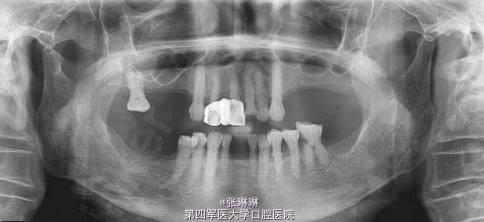

患者女,65岁,因牙齿多颗牙缺失,前去修复科治疗。

口内检查及全景片检查:14、15、16、24、25、26、27、31、37、41、46、47牙缺失,17、32、34、35、36、42、44、45牙慢性牙髓炎。

根据龋坏程度、患者的症状、修复需要,且对收费及牙髓处理均征得同意后第一次行右下4、5,左下4、5、6;第二次行左下2,右下2 ,右上7一次性根管治疗术, 术后见右下4,左下4均有侧支充填,且位置对称,左下6近中根中部有侧支;左下5、左下6远中根管均多个开口。 热牙胶垂直加压后有封闭剂和牙胶超填,但无术后反应。